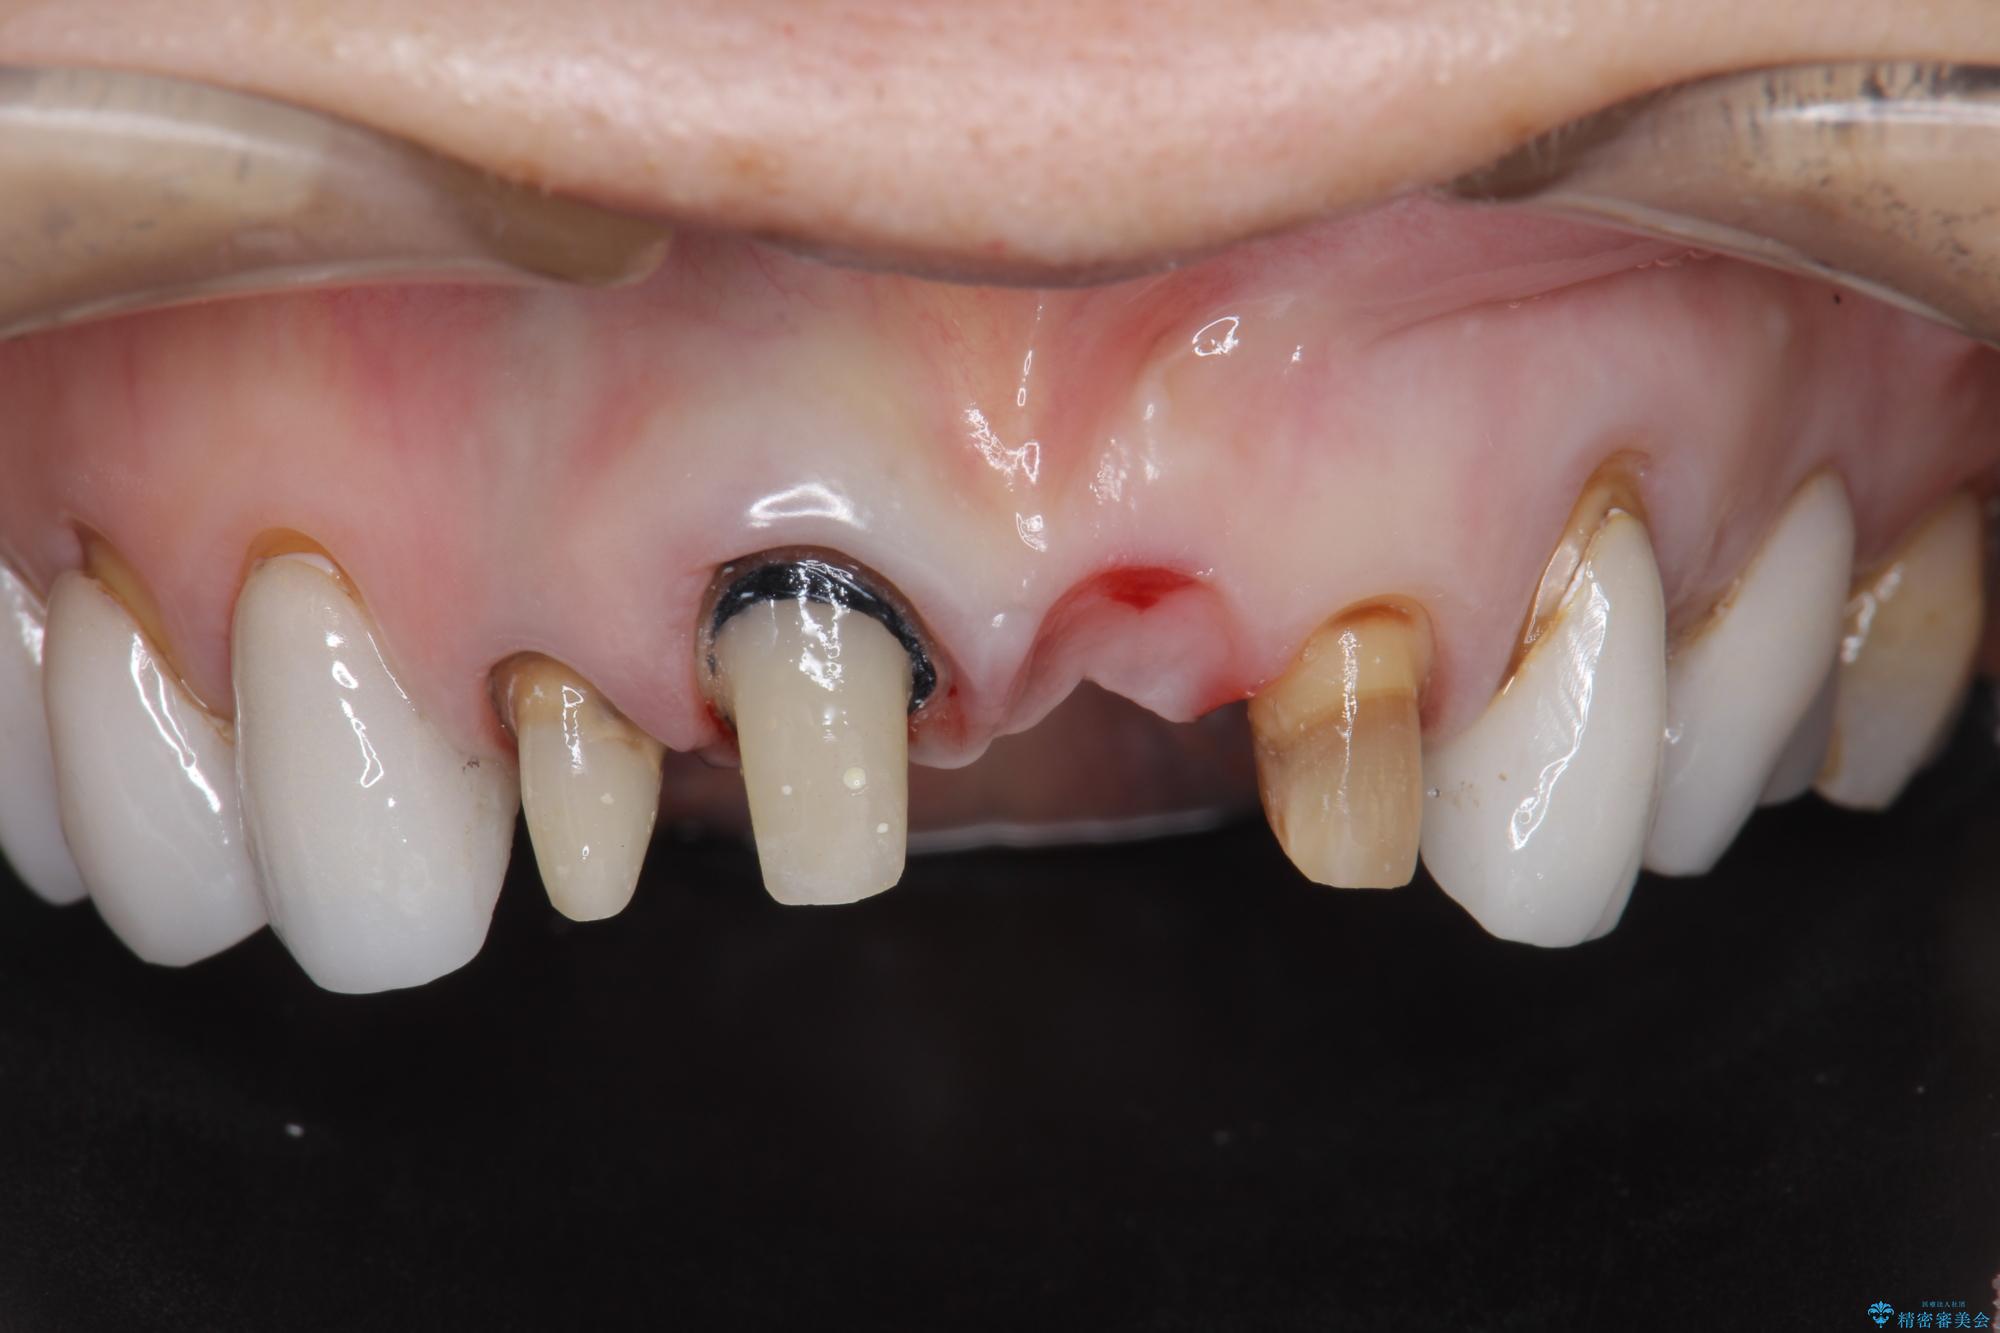

[ セラミック治療 ] 歯ぐきの際の黒ずみを改善したい

- 歯ぐきとセラミックの間の黒ずみが目立つので、きれいに治してほしい。と希望され来院されました。

歯ぐきの位置が変化しクラウン下の歯が見えるようになってしまったことで、審美障害が生じている状態です。

クラウンマージンの再設定を行うことで、黒ずんだ部分を再度覆い、審美障害を改善します。